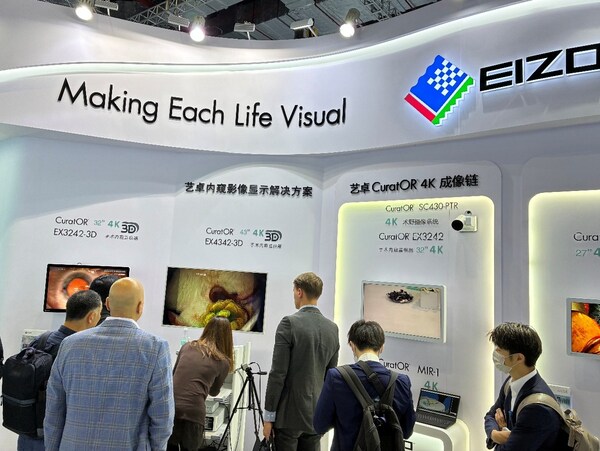

凭借硬核的产品实力,艺卓展台人气高涨。艺卓日本总部、德国公司及中国团队的资深专家们在展会现场为参观者们提供专业的技术讲解、产品演示与方案咨询。

本届展会,艺卓精心特意打造了模块化的展示空间,特设"新品首发""艺卓放射影像显示解决方案"、"艺卓内窥影像显示解决方案",以及"艺卓CuratOR4K成像链"等多个专区,覆盖了诊断、手术、临床监护等全场景应用。

为全方位满足医疗机构多元化、高精度的临床使用需求,艺卓在首展新品的同时,呈现了高端放射诊断与报告解决方案、人体工程学临床工作站解决方案,以及适配手术室严苛环境的先进视觉技术解决方案三大核心产品线,覆盖临床诊疗中的多个应用场景,为医疗工作提供全流程支撑。